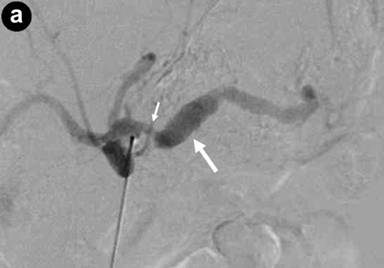

Bleeding from the papilla of Vater was not evident with upper gastrointestinal endoscopy on the day of admission. Conservative treatment was performed for the acute pancreatitis because the patient was hemodynamically stable. The epigastric pain and the serum amylase level improved after conservative treatment. During hospitalization, however, the patient developed the same epigastric pain as that usually experienced before melena, and the serum amylase level was found to be 243 U/L. We performed emergency upper gastrointestinal endoscopy to confirm the diagnosis of hemosuccus pancreaticus. Bloody pancreatic juice was observed exuding from the papilla of Vater (Figure 2). We concluded that the recurrent episodes of epigastric pain and melena had been caused by hemosuccus pancreaticus. There were no clinical or laboratory findings suggestive of arteriosclerosis or vasculitis, and diagnostic imaging showed no evidence of chronic pancreatitis or pancreatic pseudocyst. We therefore considered that the splenic aneurysm was due to segmental arterial mediolysis. We planned transcatheter arterial coil embolization for the splenic aneurysm, and the patient was discharged. However, he was re-admitted before the scheduled embolization because of sudden epigastric pain and, when tested, his serum amylase level was found to be 631 U/L. CECT revealed leakage of contrast medium into the main pancreatic duct from the aneurysm, along with dilatation of the upstream main pancreatic duct (Figure 3ab).

Figure 3. a. Contrast-enhanced computed tomography (CECT) revealing a leakage of contrast medium into the main pancreatic duct from a fusiform aneurysm of the middle-distal splenic artery (small arrow), along with dilatation of the upstream main pancreatic duct (large arrow). b. 3D-CT angiography showing a leakage of contrast medium from a fusiform aneurysm of the middle-distal splenic artery (arrow). |